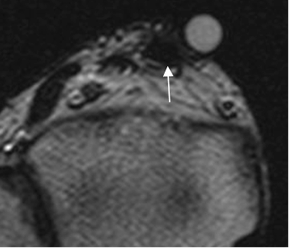

Fig 69. Tendinitis crónica del tibial anterior.

A: RM axial en T2. Engrosamiento del tendón tibial anterior. (Marca sobre la región de interés).